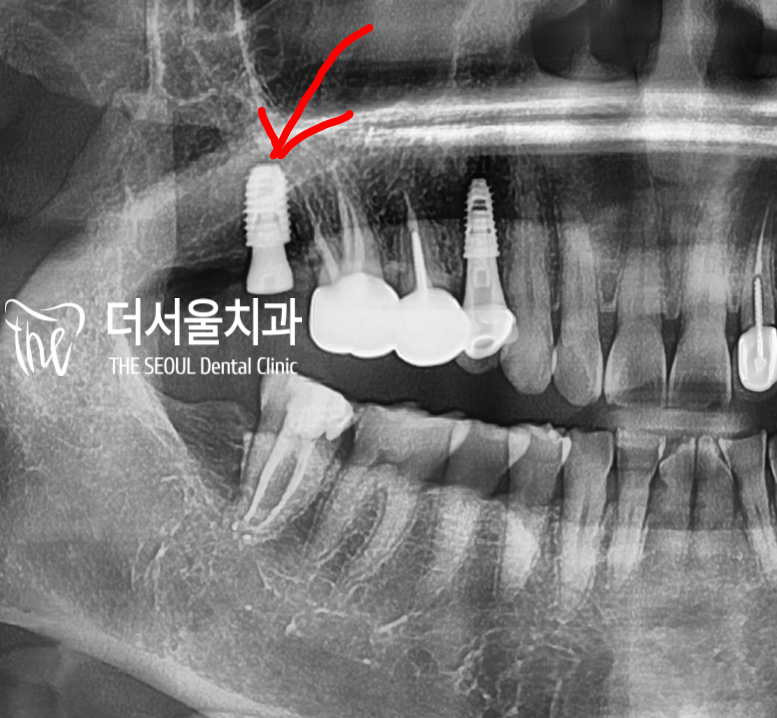

『첫번째 수술

2017년 5월』

이미 #14 소구치의 결손으로 찾아오셨습니다.

이 때가 아마 첫 내원이셨던거 같습니다.

#15번과 #13번 사이의 공간이 협소했기에,

시술 과정 자체가 힘들긴 했었습니다.

이미, 골 퇴축(Bone defect)이 상당히

진행 되었었고 골폭 또한 좁았기 때문에

뼈이식을 진행하면서 시술을 도와드렸었죠.

이렇게, 내비게이션임플란트 의 도움을

받아서 나름 쉽게 좋을 결과를 안겨드렸었습니다.